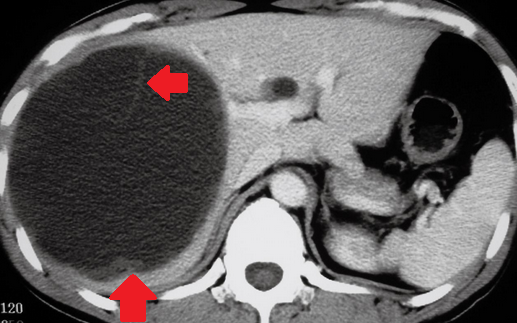

Abdominal CT scan. Hemorrhagic rupture of a simple hepatic cyst without active hemorrhage. The presence of free intraperitoneal fluid is noted (Courtesy Dr. V. Penopoulos)